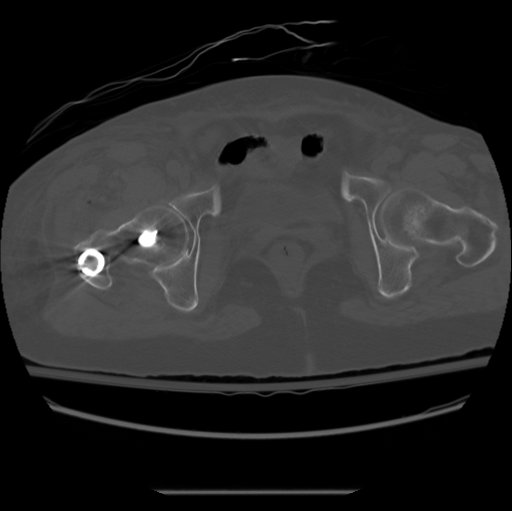

Malrotation

Incidence

Unknown

> 100 may be prevalent in up to 40% of patients

Probably not relevant unless > 300

May be associated with anterior knee pain and/or hip pain

Diagnosis

A. Clinical

- difficult

- probably best to assess internal and external rotation of the hip

- when swelling goes down can assess internal and external rotation of the foot

B. CT

- axial cuts of the femoral neck and the femoral condyles

Prevention

A. Match cortices on the proximal and distal fragment

B. Both patellas pointing anterior

- match lesser trochanter position of both hips

Treatment

A. Early

- remove distal locking screws but leave in wires

- correct rotation based upon CT measurement

- insert new distal locking screws at the predetermined angle from previous screws

B. Late

- may need osteotomy

Vergano 2020 Summary article

https://www.ncbi.nlm.nih.gov/pmc/articles/PMC7944689/pdf/ACTA-91-03.pdf